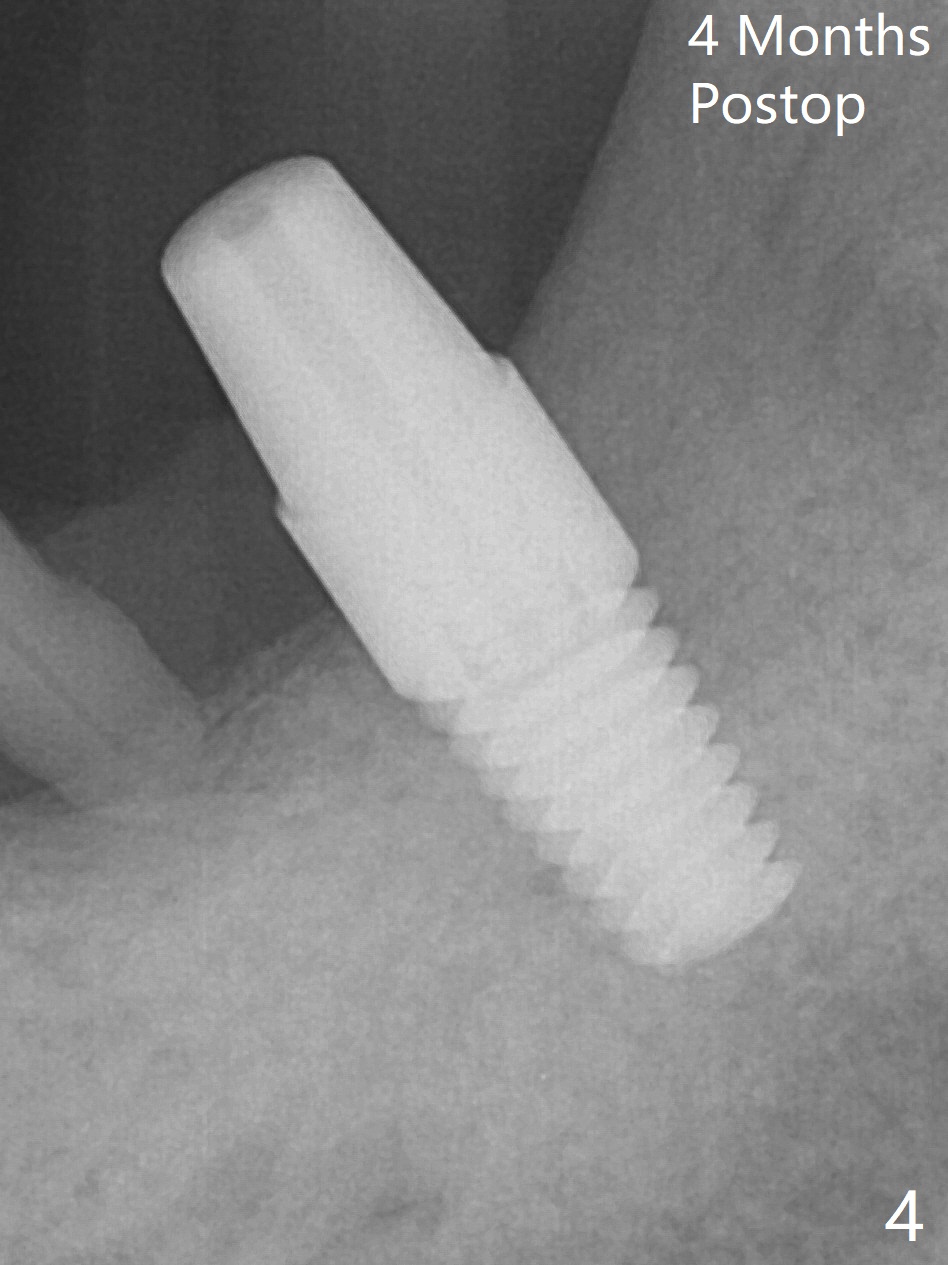

After extraction of the mesioangular tooth #17, initial osteotomy at #18 is 11 mm in depth with sudden empty feel (without pain with infiltration anesthesia); when a parallel pin is inserted, it goes down more than expected (Fig.1). Subsequent osteotomy is strictly controlled at the depth of 11 mm for 2.5 and 3.0 mm reamers. When 3.5 and 4.0 reamers are being used for ~ 9 mm, pain is confined to the coronal portion of the osteotomy, apparently associated with infection from the socket of #17 or from the distal apex of the tooth #19 (scaling & root planing done earlier). After addition of local anesthetic (infiltration), a 5x11 mm tap is inserted (Fig.2). With sufficient clearance from the Inferior Alveolar Canal (Fig.1-3 red dashed line), block anesthesia is administered. A 5x11 mm Tatum implant is placed with >50 Ncm (Fig.3). A 4.5x5 mm abutment is placed to increase retention of periodontal dressing. Impression is taken 4 months postop (Fig.4). The tooth #19 is symptomatic 7 months post #18 cementation.